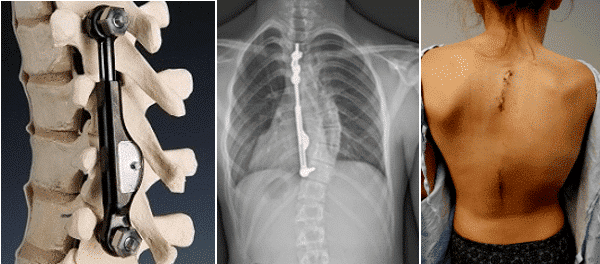

Yet another advancement that is still in its growing phase. Apifix is a newly developed surgical treatment for scoliosis which is of a non-fusion variety. It is told to reduce the curve point and is only said to be used when the risk of progression is low.

Although it is a promising procedure in scoliosis treatment, this procedure also does not eliminate your need for undergoing surgery under anaesthesia. Apifix is an implant device that will be screwed on to the spine as seen in the picture. It is a time-consuming process which is done in two phases. Firstly, the implantation will require surgery to be performed on your back that will result in a scar.

Secondly there will be “drill holes” made on the spine to screw the device. Although called as a “minimally invasive procedure”, this will require you to undergo a first surgery and does not clearly elude the need for further surgeries.